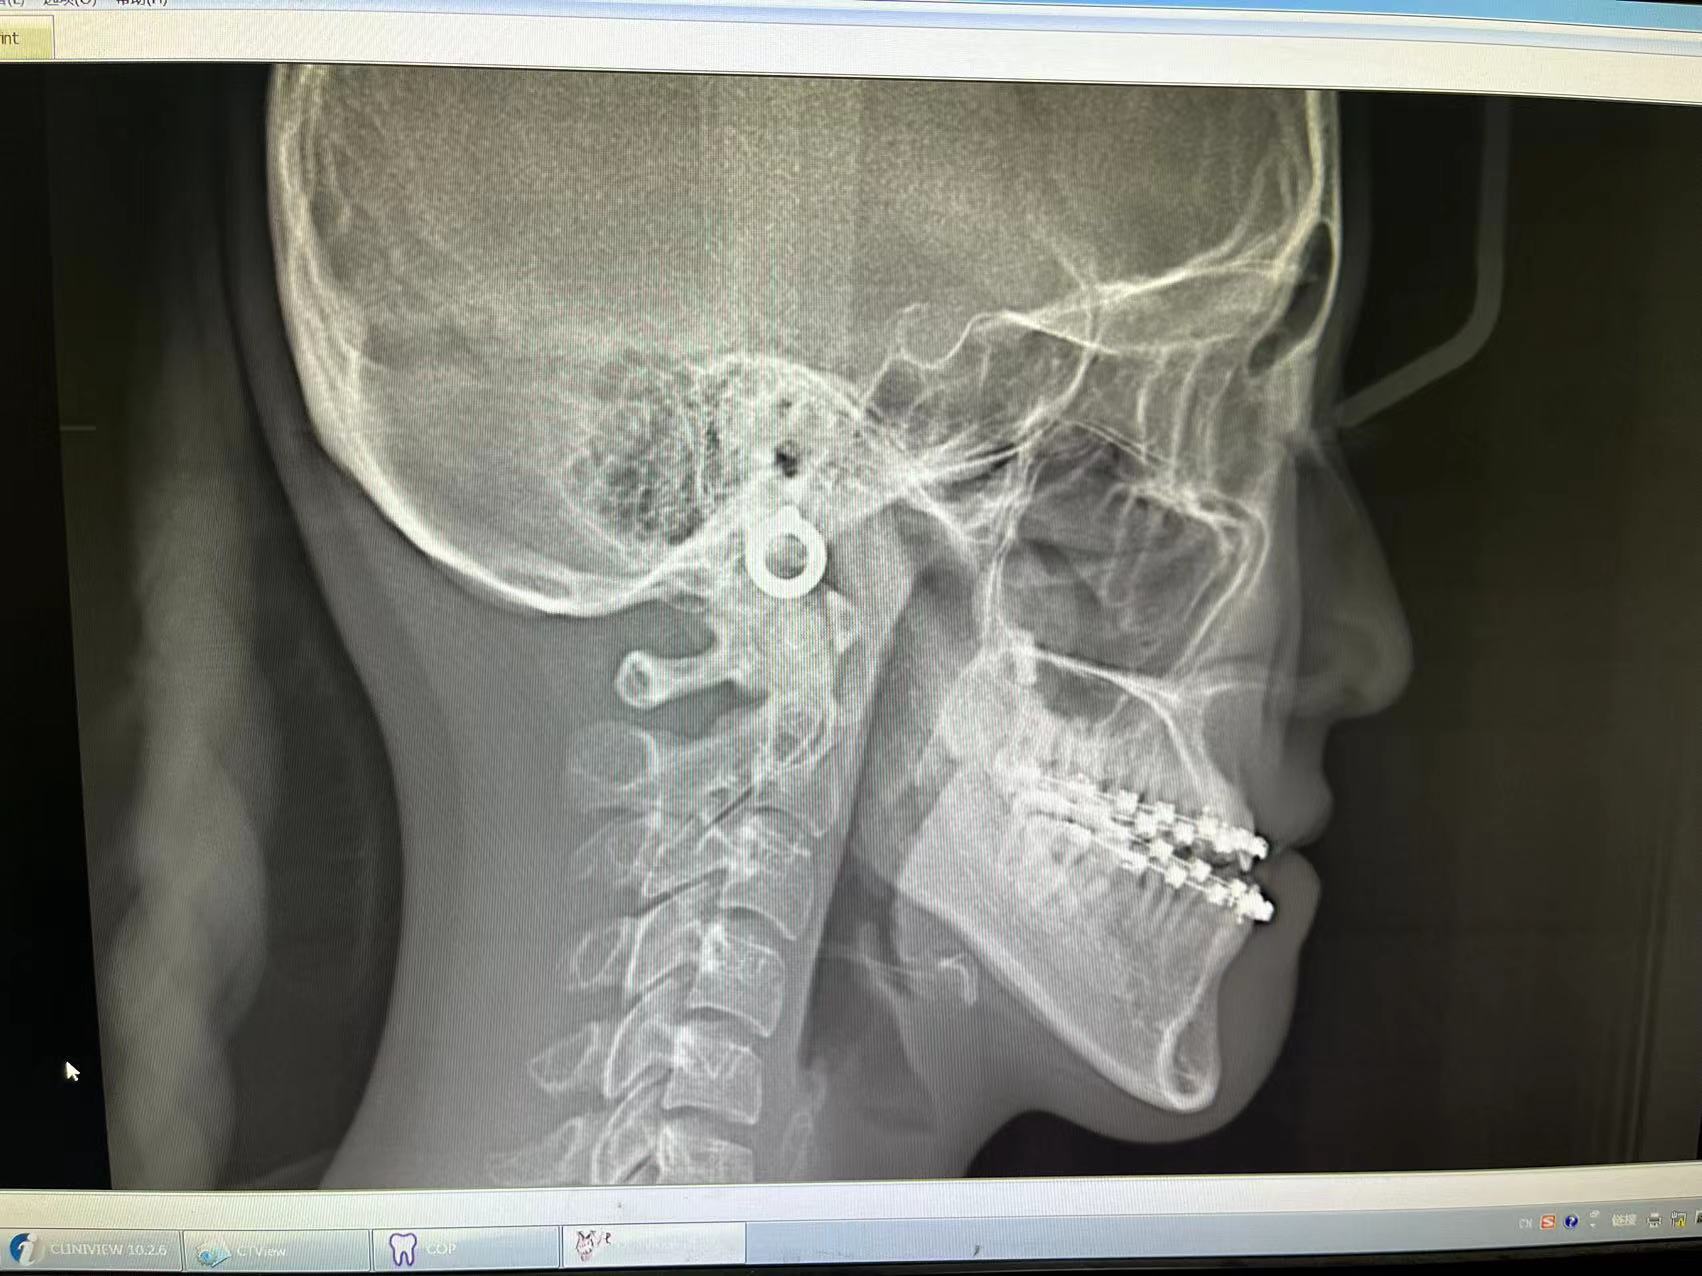

帶牙套后牙齒有輕微的松動是正?,F(xiàn)象,這時候用手稍使勁搖晃牙齒會有輕微松動感,拍片后顯示牙齒的牙周膜腔隙增寬,這屬于正常。如果,用手指輕輕觸碰就感到牙齒很松,那就要警惕了,建議告知醫(yī)生盡快就診。另外,要感受在咬合,咀嚼東西時,是否有個別牙先接觸的情況。尤其是隱形患者,在不戴牙套咬物時,是否有這種咬合早接觸的情況。如果有,需要盡快就醫(yī)。如果不能馬上就醫(yī),早接觸的情況又比較嚴(yán)重(某個牙很疼或者很酸),那可以嘗試暫時戴牙套吃飯,并且放慢更換牙套的速度。有牙周炎的患者需要尤其注意,矯正后如果有個別牙松動明顯加重,要及時感知,并告訴您的正畸醫(yī)生。

關(guān)于矯牙的疑問 對于矯牙,想必大家有很多疑問,到底應(yīng)該幾歲去矯牙?矯完牙牙齒是不是會松?矯牙過程會不會很丑?。。。。。。今天在“廣州日報健康管家”看到一篇好文,特別在這跟大家分享,希望能夠解決大家的疑問。Dr.薛對其中的內(nèi)容作了適當(dāng)?shù)难a(bǔ)充,請細(xì)細(xì)閱讀 疑問1:是不是只有小孩子可以進(jìn)行牙齒矯正? 關(guān)于矯牙,很多人認(rèn)為,那只是青少年的專利,年紀(jì)大的人矯牙,牙齒會松。但其實(shí)牙齒的移動是任何年齡都存在的生理性骨改建過程,因此,牙齒矯正并非青少年的專利,只要牙周條件良好,任何年齡都可以矯牙。不過,相對而言,只是成年人矯牙,由于種種條件的限制,矯治難度可能有所提高,時間也可能會相對長一些。 至于對矯牙可能帶來的牙齒松動或掉牙的擔(dān)心,其實(shí)真正引起牙齒松動和掉牙的原因主要是牙周病,而不是矯牙。因?yàn)楫?dāng)口腔環(huán)境差時,牙齒表面的牙菌斑與唾液中的礦物質(zhì)進(jìn)行作用,會形成牙石,牙石慢慢堆積,會感染其周圍的組織造成牙周炎。而牙齒周圍的組織,比如牙槽骨,會因牙周炎而發(fā)生吸收,牙根被牙槽骨所包繞的面積隨著牙槽骨的吸收而減少,最后就會發(fā)生松動和脫落。在矯牙過程中,如果能夠做到認(rèn)真刷牙,及時將托槽周圍清理干凈,并使用牙線或間隙刷等對牙齒進(jìn)行徹底清潔,不會發(fā)生松動和脫落。當(dāng)然,在矯治中,牙齒必須松動才能移動到新的位置,但是這個松動度是非常小的。矯治完成后通過保持器的戴用,牙齒在新的位置上自然會長牢固。“此外,如果戴上矯正器有劇烈疼痛,肯定是不正常的,應(yīng)及時就醫(yī)?!? 疑問2:是不是一定要等到孩子12歲左右才去矯牙? 很多家長都知道12歲左右是矯牙的最佳時機(jī),因此,都認(rèn)為孩子牙齒不整齊不要緊,只要到時去矯正就好了;還有的家長認(rèn)為,孩子平時學(xué)習(xí)緊張,等中考或高考結(jié)束后,再去矯牙也不遲。但是,這往往會使孩子錯過最佳矯正時機(jī)。 很多骨性畸形,最好在青少年處于生長發(fā)育高峰期前進(jìn)行治療。一般情況下,女孩在11~13歲、男孩在12~15歲是比較好的矯牙時期。如果錯過了這個時期,有些頜骨畸形就得不到理想的矯治。再比如孩子如果有小下巴或者兜齒,4歲就可以開始矯治了?!昂⒆幼詈迷?歲前就去看看正畸科醫(yī)生,請專業(yè)的正畸醫(yī)生對孩子是否需要做牙齒矯正進(jìn)行評估,以免錯過最佳治療時機(jī)。如果發(fā)現(xiàn)孩子很小時就有小下巴或者兜齒,更應(yīng)盡早看正畸醫(yī)生,一旦明確孩子有骨骼發(fā)育異常,就應(yīng)該及早進(jìn)行干預(yù)治療,可將這種發(fā)育異??刂圃谝欢ǔ潭葍?nèi)?!? 疑問3:矯正牙齒的時候拔掉幾顆大牙可以瘦臉嗎? 網(wǎng)上有不少明星拔牙瘦臉的傳聞,因此很多人誤以為,在矯牙時可以多拔掉幾顆牙,就可以變“錐子臉”了。但是,牙齒矯正是需要拔掉一些多余的牙,矯牙前的拔牙絕對是不能亂拔的。 如果把人的牙齒平均分為四個象限,上下左右各有一個象限,每個象限的前牙和大牙之間有兩顆“過渡牙”,也稱為“雙尖牙”。通常情況下,矯牙前的拔牙主要就拔兩顆過渡牙中的一顆,這是因?yàn)檫^渡牙的功能不大,拔掉一般不會對口腔健康和美觀造成負(fù)面影響。“而以下牙齒一般是不拔的:一是口腔前面的六顆前牙不能拔,因?yàn)榍把缹谇幻烙^影響特別大;二是大牙不能拔,因?yàn)榇笱涝诰捉罆r起重要作用。因此,網(wǎng)上流傳的拔掉幾顆大牙就可以變錐子臉的說法是不科學(xué)的?!薄驹谶@里,我要補(bǔ)充一下,前牙和大牙并不是絕對不能拔,而是應(yīng)該根據(jù)每個人的情況去進(jìn)行個性化的方案設(shè)定。例如大牙有爛牙,而智齒存在,可以考慮拔除大牙。到底要拔什么牙,應(yīng)該經(jīng)過專業(yè)醫(yī)生的充分檢查和評估之后,再做決定哦?!? 疑問4:矯牙是不是一定要戴牙箍,變成“滿口鋼牙”? 很多愛美的成年人通常對矯牙下不了決心。在他們看來,只要是矯牙,就意味著在長達(dá)兩年多的時間里,必須以“滿口鋼牙”示人。其實(shí),現(xiàn)在矯牙,不一定必須“滿口鋼牙”。 傳統(tǒng)的固定矯治的基本裝置都是由托槽(俗稱“牙套”)和鋼絲構(gòu)成的,在整個矯正過程中,都需要以“滿口鋼牙”示人,的確有影響美觀、清潔不便、帶來口腔不適的缺點(diǎn)。但是,現(xiàn)在在牙齒矯治中,已越來越多地使用無托槽隱形矯治。 無托槽隱形矯治已沒有傳統(tǒng)固定矯治的托槽和矯正弓絲等裝置,而只是通過特殊的牙科材料(俗稱“隱形牙套”)包裹牙齒產(chǎn)生矯治力。這種矯治器用一種透明的高分子材料制作,沒有托槽、鋼絲等結(jié)構(gòu),需要兩個星期換一副,每一副矯治器由計(jì)算機(jī)輔助設(shè)計(jì),精確預(yù)設(shè)牙齒移動的量,當(dāng)一副矯治器按照要求配戴完成時,牙齒便精確移動到預(yù)設(shè)的位置。 由于這種牙套是透明的,佩戴時不易被人察覺,異物不適感也較小,也便于清潔,進(jìn)食時摘下牙套,進(jìn)食完清潔牙齒和牙套后再戴上牙套即可。 這種無托槽隱形矯治要求對牙齒的移動進(jìn)行精確預(yù)設(shè),因而對醫(yī)生的專業(yè)性要求也比較高。此外,也要求患者有較好的依從性,必須嚴(yán)格按照醫(yī)生的要求,每天佩戴足夠時間的隱形矯治器。 比較一下,傳統(tǒng)固定矯治牙箍(左)和隱形牙套(右) 隱形牙套勝在美觀,還可自己摘取。 (圖片均來自網(wǎng)絡(luò))